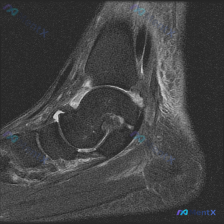

拿到这张踝关节MRI矢状位T2加权影像,问题提示是「软组织积液」,整理一下完整的读片和分析思路给大家参考。

这是一张对比度良好的踝关节矢状位T2加权(大概率脂肪抑制)序列,能清晰看到胫骨远端、距骨、跟骨等主要解剖结构,没有明显伪影。

- 距骨穹窿前部软骨/软骨下骨: 可见局限性清晰的高信号病灶,这是整个影像最核心的异常

- 胫距关节间隙: 可见明显条带状液性高信号,提示存在关节积液

- 距骨颈部前方+胫骨前缘: 可见小的骨赘(骨刺)形成,提示慢性改变

其他结构:跟腱形态正常无断裂,皮下软组织信号均匀,其余骨髓信号都没有明显异常。

一开始看到「软组织积液」的描述很容易被带偏,但仔细看影像就会发现:积液其实是在胫距关节间隙内,并不是关节外的软组织积液,所以整个诊断思路必须聚焦在关节内病变。

核心线索其实是两个:「距骨穹窿前部局限性高信号」+「关节内积液」,骨赘是次要的伴随改变。